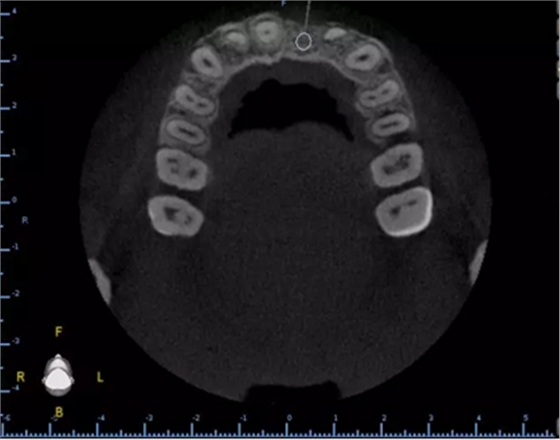

1.術(shù)前CT

2.術(shù)前植體設(shè)計(jì)

3.術(shù)前導(dǎo)板設(shè)計(jì)